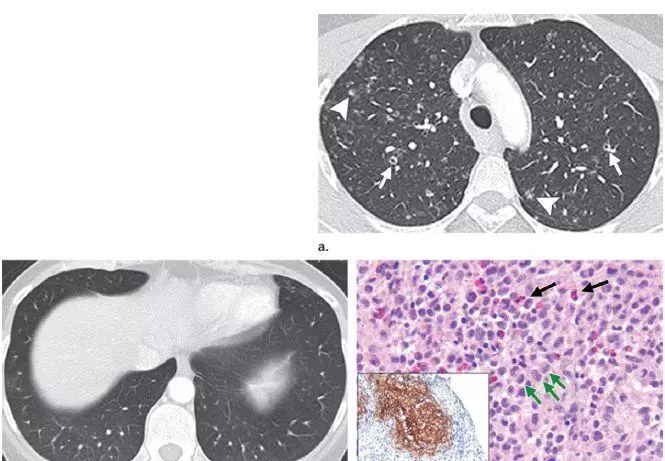

早期疾病薄层断层扫描(CT)可显示1–10mm的小叶中心结节或者空洞(图1)。随着病情的发展,囊性病变逐渐取代结节,表现为厚或薄壁囊腔,形态多不规则(图2)。结节和囊性病变通常累及双肺上中野,肺尖和肺底以及肋膈角常不受累。约25%的患者由于胸膜下囊腔破裂导致自发性气胸,累及双侧并且可以反复发作,这是本病的首发症状(图3)。终末期疾病的特点是肺过度充气以及广泛的囊腔,形成终末期肺气肿(图4)。薄层CT具有特征性人口统计学分布特点及临床表现,是PLCH临床诊断的重要依据,从而避免肺活检。在儿童中,薄层CT表现与成人相似,但更病变更广泛(图5),并且与未发现与吸烟有关的病灶。

图1 44岁女性PLCH患者。a 薄层CT显示边界不清的结节影,主要位于双肺上叶,这些结节是典型PLCH细胞浸润早期表现。部分结节中心部分是透亮的,提示将要囊变。b CT图像显示双肺底部未受累。c 组织病理学检查,显微镜下图像显示细胞核皱缩、折叠的朗格汉斯细胞和嗜酸性粒细胞。CD1a免疫组化染色显示成片朗格汉斯细胞被染成特征性的棕色。